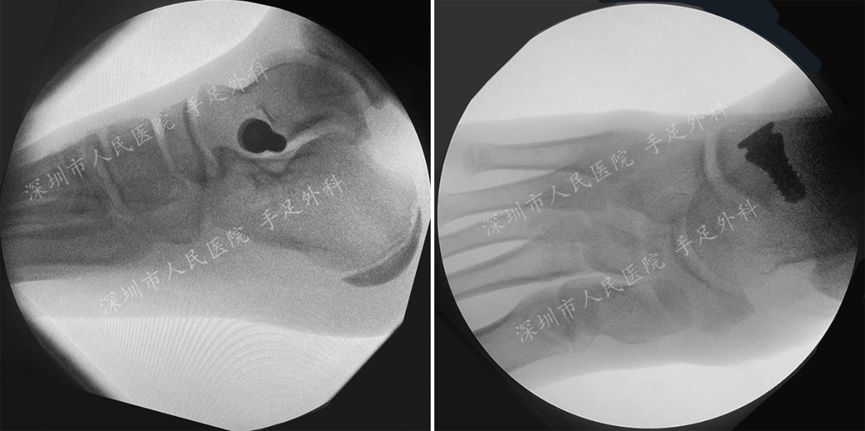

(一) 拇外翻

拇外翻畸形是一种足部常见的畸形,主要表现为拇趾在第一跖趾关节处向外侧偏斜移位,严重者可伴有疼痛,影响患者的日常活动,同时会影响足部的美观及日常鞋型的选择。本中心采用微创和传统手术方法矫正不同类型的拇外翻。

图1:拇外翻常合并拇囊炎,位于拇趾跖趾关节内侧,常伴有红肿和疼痛。

图2:经截骨矫形后(Scarf截骨),拇外翻畸形被矫正。